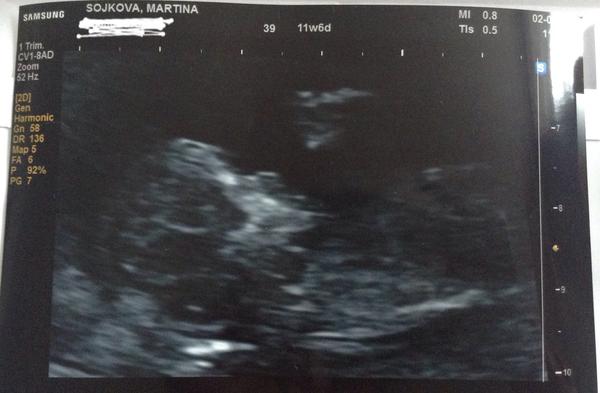

Jinak já jsem po 1. IVF, už 7. den od ET jsem měla //, minulý týden na UTZ potvrzeny dvě bublinky, dneska jsem 5tt+4 a už se do ničeho nevejdu - mám dojem, že s dvojčátkama bude všechno mnohem intenzivnější a rychlejší 😀

@kanka80 kdyz jsem tam byla poprve, tak jsem byla 5+6tt a ted 7+6tt tak ja nevim co se stalo. Ale jednou jsem se vzbudila a nebylo mi zle a mela jsem pocit ze uz mam jen jedno mimi . Pak se nevolnost vratila a ja to uz nejak neresila. Ale stale mam pocit ze su dve, to by jsme ho ale videli ne? Krom mimca tam byl jeste nejaky zloutkovy vacek, ten ale prej vyzivuje tohle mimi. Jsem zmatena..

@tynka07 Ahoj, dekuji. Ano to jedno je zdrave. Jsme po screeningu a byl negativni. Ja nespinila ani me nic nebolelo. Ale jedno rano jsem se vzbudila a mela pocit ze je tam jen jedno no a to se potvrdilo. 😖